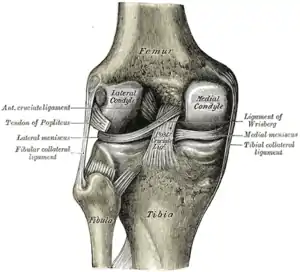

| Knee | |

Skeletal components involved in the unhappy triad include: patella, femur, tibia. No muscles are directly involved in this injury, only ligaments; However, strengthening the hip flexor and hip extensor muscles may help alleviate the injury.

The medial collateral ligament, posterior cruciate ligament, anterior cruciate ligament, and lateral collateral ligament are the four primary ligaments of the knee. The medial and lateral collateral ligaments primarily provide support to varus and valgus forces whereas the anterior and posterior cruciate ligaments prevent anterior and posterior translation of the tibia on the femur.[2]

The classic O'Donoghue triad is characterized by an injury to three knee structures (in order):

- the anterior cruciate ligament

- the medial meniscus (however, lateral meniscus[1] injuries are more commonly seen among athletes, leading to the definition of the O'Donoghue triad most commonly used today.) [3][4][5]

- the medial collateral ligament (or "tibial collateral ligament")

The anterior cruciate ligament

The anterior cruciate ligament is one of the four crucial ligaments in the knee. It originates from the lateral condyle of the femur and goes to the intercondyloid eminence of the tibia. Its function is to provide stability in the knee and minimize stress across the knee joint. It also restrains excessive forward movement in the leg and limits rotational movements in the knee.